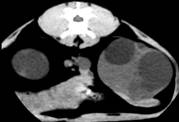

Ниркова миска візуалізувалась у всіх

випадках у вигляді вузької гіподенсної щілини, контури якої залежали від

ступеня гідронефротичних та кістозних змін органа (рис.).

Рис. 9. КТ

кота. Полікистоз нирок у стадії субкомпенсації. Візуалізація миски лівої нирки

Рис. 10. КТ

кота.

Полікистоз

нирок у стадії субкомпенсації. Розширення миски правої нирки (а), кістозні

утворення різної інтенсивності (б, в)

Аналізуючи отримані дані, слід

зазначити, що застосування методу комп’ютерної томографії для діагностики полікистозу

нирок у кішок є можливим. При цьому, використовуючи різні

прийоми та режими сканування, можна отримати дані, що дозволяють

характеризувати контури органа, розмір та вміст кістозних утворень, зміни

ниркової миски. Дослідження в динаміці дозволяє скласти виразну картину

перебігу патології, визначити характер кістозної рідини та зробити висновки

щодо подальшого лікування тварини. Між тим слід зауважити, що застосування

магнітно-резонансної комп’ютерної томографії у ветеринарній медицині в цілому

супроводжується певними труднощами, пов’язаними передусім із відсутністю

відповідного обладнання, тоді як широке використання апаратури у закладах

гуманної медицини не видається можливим з певних міркувань. Таким чином, метод

комп’ютерної томографії є перспективним у діагностиці ниркових патологій у

кішок в цілому, і зокрема полікистозу.